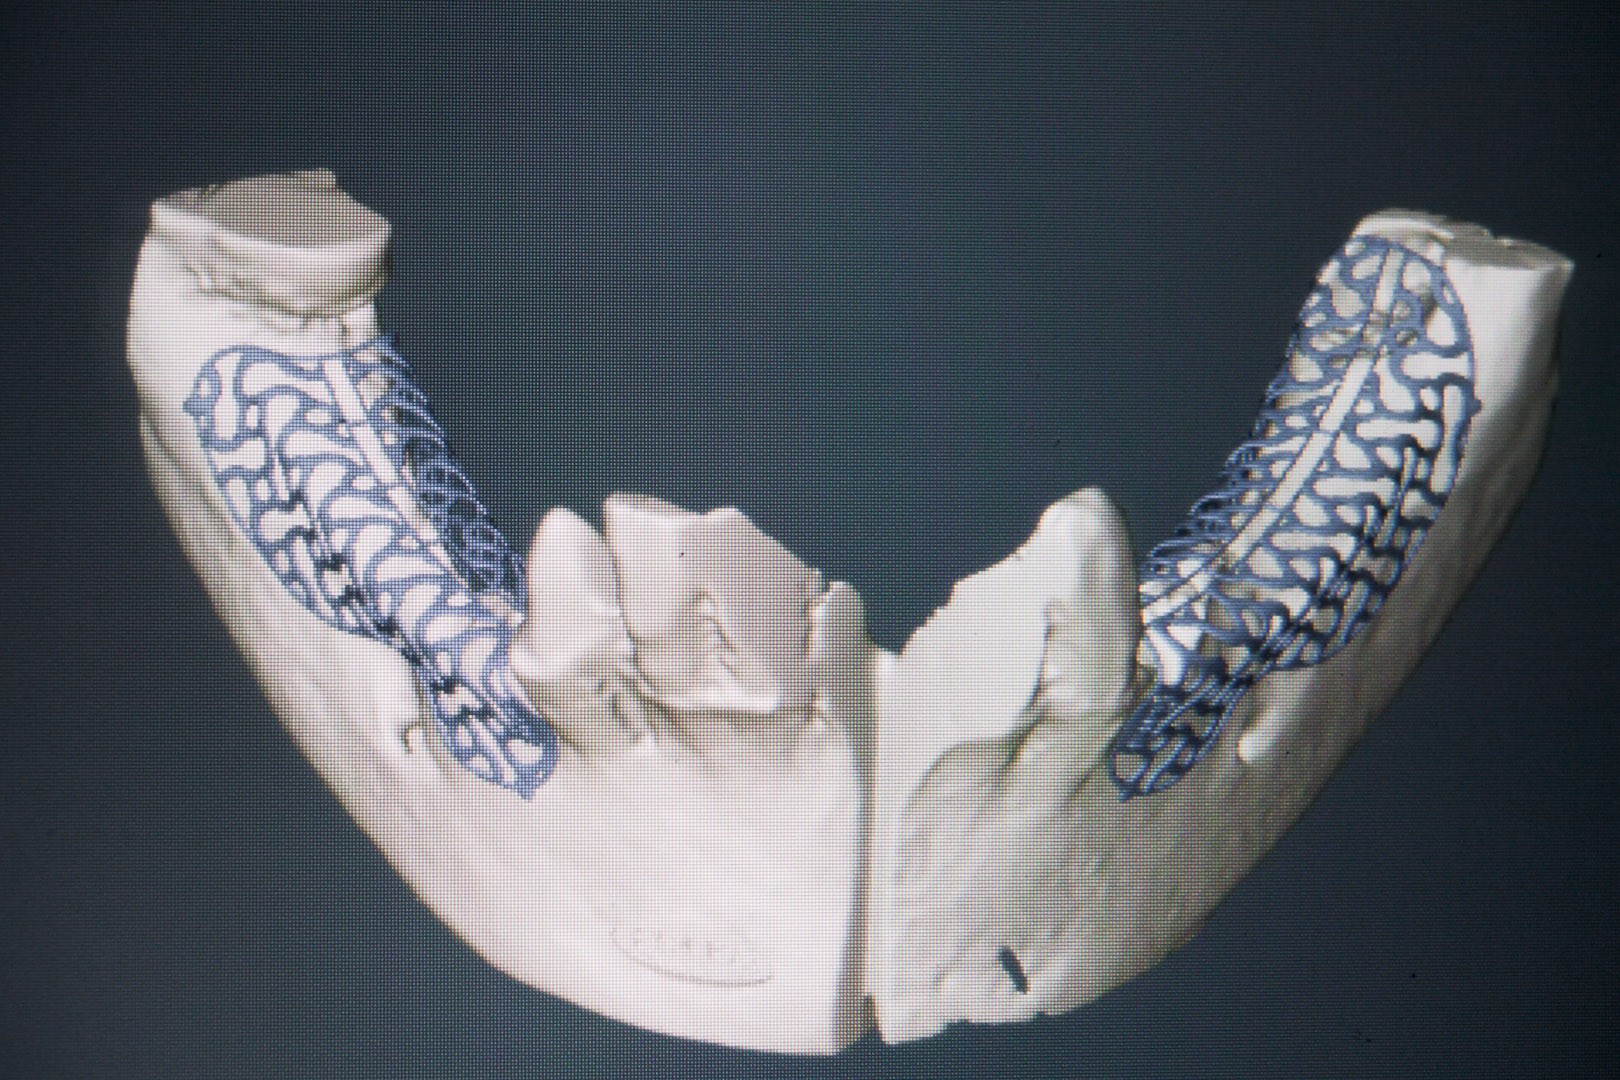

To kolejna metoda umożliwiająca precyzyjną odbudowę zadanego kształtu tkanki kostnej przy użyciu standardowych materiałów kościotwórczych, kości własnej lub PRF oraz zewnętrznego rusztowania w postaci siatki z biozgodnego stopu tytanu. Siatka jest indywidualnie projektowana w technologii CAD CAM i następnie drukowana dla konkretnego przypadku.

Dotychczas stosowane stabilizatory zewnętrzne w formie siatek tytanowych używane do regeneracji kostnej lub w zabiegach odtwórczych w chirurgii szczękowo-twarzowej uwzględniały materiały ręcznie doginane i formowane podczas zabiegu operacyjnego. Zastosowanie technologii CAD CAM dla potrzeb druku materiałów przeznaczonych do indywidualnej rekonstrukcji kostnej znacznie poprawiło precyzję i jakość uzyskiwanych efektów. Wdrożenie biozgodnych stopów tytanu do druku siatek zdecydowanie ograniczyło odsetek powikłań zapalnych.

Siatki stanowią stabilną obudowę – ograniczenie nadające kształt regenerowanej kości przy użyciu upakowanego pod nią materiału. Utrzymują i stabilizują rozdrobniony granulat kościotwórczy, co jest warunkiem prawidłowego procesu gojenia, jednocześnie nadając anatomiczny kształt i zakres odbudowie kostnej sprzed jej zaniku.

Precyzja projektu druku siatki bazuje na dokładności odwzorowania kształtu kości w stożkowej tomografii komputerowej CBCT, co zapewnia ich dobre przyleganie do podłoża kostnego oraz ogranicza powstawanie powikłań w postaci obnażania się siatek.

Precyzja projektu oraz materiał, z którego wykonana jest siatka (biozgodny stop tytanu), powodują, że obnażenie się siatki nie zaburza procesu gojenia i regeneracji kostnej. Wymaga jedynie większej ilości kontroli pozabiegowych oraz wzmaga czujność higieniczną zarówno ze strony lekarza, jak i pacjenta.

Ten rodzaj odbudowy kostnej stosowany jest w sytuacjach złożonych, trójwymiarowych 3D ubytków kości, przy których standardowe metody odbudowy są niewystarczające. Ilość kości, którą możemy uzyskać, stosując tę metodę, to nawet kilka centymetrów sześciennych.

Metoda rekonstrukcji kostnej w oparciu o indywidualnie drukowane siatki z tytanu dla implantacji wszczepów śródkostnych stosowana jest najczęściej jako dwuetapowa. W pierwszym etapie odbudowywana jest kość, natomiast implanty wszczepiane są po okresie 4–6 miesięcy. Na wgojenie implantów oczekujemy od 4 do 6 miesięcy w zależności od miejsca ich lokalizacji. Siatka tytanowa po spełnieniu swojej funkcji rusztowania dla odbudowującej się kości jest następnie usuwana w dniu wszczepienia implantu. Jeżeli kość spełnia odpowiednie warunki, istnieje możliwość zastosowania modyfikacji siatki tytanowej, która umożliwia jednoczesne wprowadzenie implantów wraz z odbudową kostną. Wariant ten skraca czas od pierwszego zabiegu do wykonania gotowych koron protetycznych na wprowadzonych implantach.